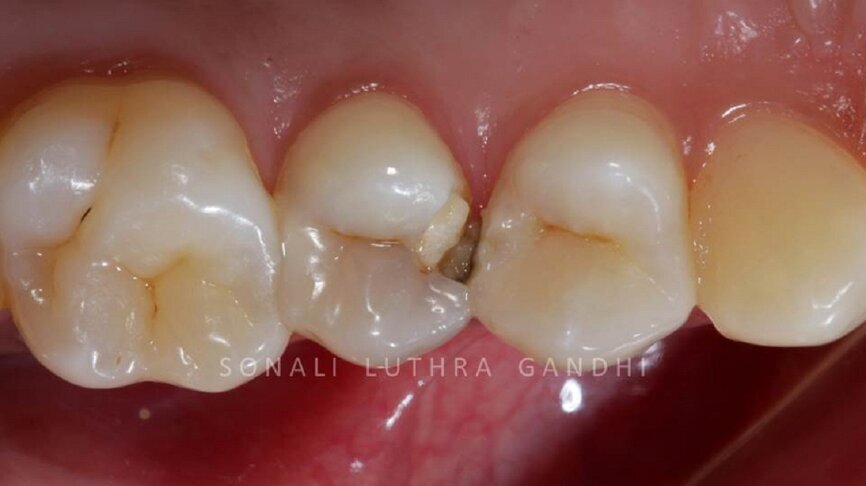

Management of posterior proximal restorations. (Photograph courtesy of Dr. Sonali Gandhi)

A 25 year old female entered the clinic with a chief complaint of food lodgement in her upper right region. On oral examination tooth number 14 and 15 showed proximal carious lesions (Fig: 1). Radiographic evaluation depicted that the teeth did not require any endodontic treatment. Isolation was achieved with a rubber dam. Additional isolation was achieved by using polytetrafluoroethylene tape (PTFE) also known as plumber’s tape/ Teflon tape (Fig: 2). Excavation was performed using a small round diamond bur followed by a carbide bur in the deeper areas (Fig: 3).